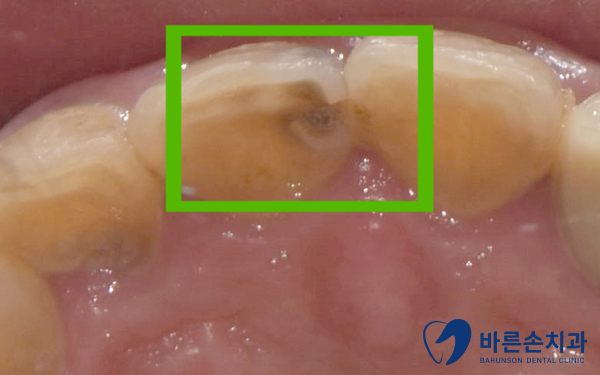

앞니에 까만게 보여요

환자분께서 앞니에 까맣게 변했다고 하셔서 치과에 내원하셨습니다.

육안상으로도 충치 진행이 많이 되어 있는게 보입니다.

안쪽으로는 충치로 구멍까지 뚫린 상태였습니다.